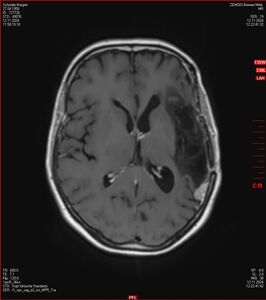

Zum Vergleich nun auch die Bilder vom 1.12.2023:

Ich denke, in den letzen 12 Monaten sind da ein paar Rezidive gewachsen,  vor 12 Monaten waren sie auch schon zu erkennen - vorher noch nicht. Nun hoffe ich auf den Rat des Spezialisten. Hoffendlich kann man etwas machen.